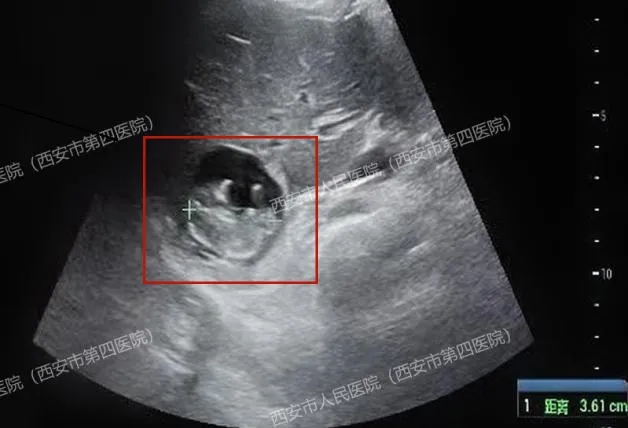

胎心搏动强劲有力,胎盘雏形也已形成,测量的顶臀径约36mm,估算的孕周近11周了!

(肝右叶有一个47x35mm的囊实性占位,附件区包块影像显示为卵巢巧克力样囊肿,并非妊娠囊)